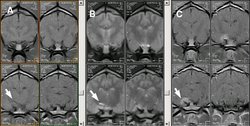

A: SE T2 dorsal. B: SE T2 sagital. C: SE T1 Gd-DTPA |